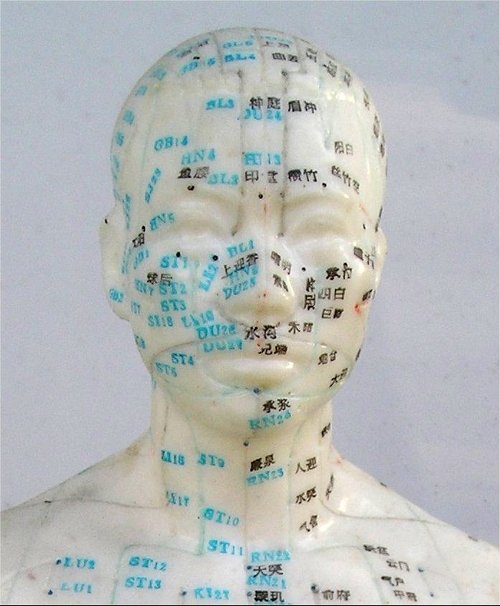

Gli aghi utilizzati nell’agopuntura aiutano ad alleviare i dolori grazie al fatto che innescano nell’organismo la produzione di una sostanza chimica, l’adenosina, di fatto un vero e proprio antidolorifico naturale.

Lo rivelano sulla rivista Nature Neuroscience i ricercatori del Center for Translational Neuromedicine presso il Medical Center dell’Università di Rochester, che inoltre suggeriscono come l’agopuntura potrebbe essere doppiamente efficace se associata ad una terapia a base di deossicoformicina, un farmaco antitumorale che sembra avere la capacità di mantenere alti i livelli di adenosina nell’area trattata.

Lo rivelano sulla rivista Nature Neuroscience i ricercatori del Center for Translational Neuromedicine presso il Medical Center dell’Università di Rochester, che inoltre suggeriscono come l’agopuntura potrebbe essere doppiamente efficace se associata ad una terapia a base di deossicoformicina, un farmaco antitumorale che sembra avere la capacità di mantenere alti i livelli di adenosina nell’area trattata.